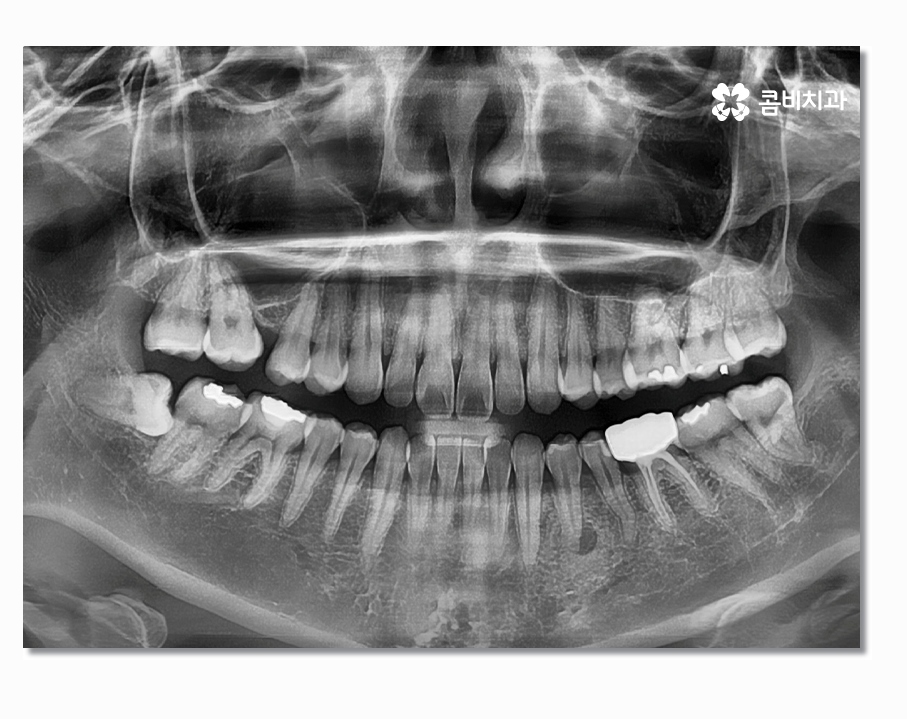

오늘은 부분매복사랑니에 대한 주제로 이야기를 해볼까 하며

부분매복사랑니는 이름 그대로 사랑니가 정상적으로

맹출이 된 것은 아니지만 잇몸 밖으로 부분적으로

나와 있는 상태를 의미하고 있어요.

사랑니는 겉으로 보이는 것과 X Ray로 살펴보는 것이

큰 차이가 있으며 사랑니의 위치와 맹출 형태, 크기 등에 따라서

발치의 과정부터 시술 난이도의 차이가 있기 때문에